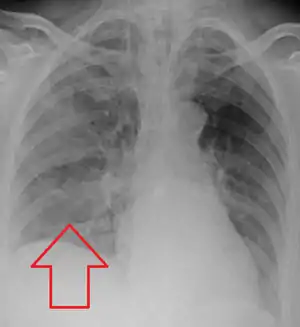

Severe aspiration pneumonia

Aspiration pneumonia is typically diagnosed by a combination of clinical circumstances (people with risk factors for aspiration) and radiologic findings (an infiltrate in the proper location).[2] A chest x-ray is typically performed in cases where any pneumonia is suspected, including aspiration pneumonia.[17] Findings on chest x-ray supportive of aspiration pneumonia include localized consolidation depending on the patient's position when the aspiration occurred.[18] For example, people that are supine when they aspirate often develop consolidation in the right lower lobe of the lung.[18] Sputum cultures are not used for diagnosing aspiration pneumonia because of the high risk of contamination.[19] Clinical symptoms may also increase suspicion of aspiration pneumonia, including new difficulty breathing and fever after an aspiration event.[6] Likewise, physical exam findings such as altered breath sounds heard in the affected lung fields may also be suggestive of aspiration pneumonia.[6] Some cases of aspiration pneumonia are caused by aspiration of food particles or other particulate substances like pill fragments; these can be diagnosed by pathologists on lung biopsy specimens.[20]